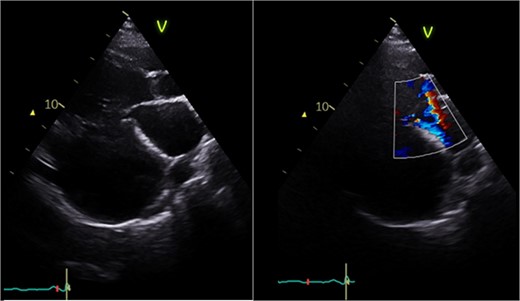

Echocardiography (Fig. 1) and cardiac magnetic resonance imaging revealed a dilated LV [left ventricular ejection fraction (LVEF) of 25%] and a large aneurysm (9.3 × 9.5 cm) involving the basal mid-inferoseptum and basal inferolateral wall with evidence of thrombus. These regions were non-viable, with transmural infarction. The mitral valve (MV) leaflets were thin but the tips, especially of the posterior mitral valve leaflet, were tethered and tented towards the LV apex resulting in severe functional MR. The left atrium (LA) was significantly dilated. The patient was admitted for medical management including aggressive diuresis. Following multidisciplinary team (MDT) discussion, surgical intervention was planned (aneurysmectomy with either MV replacement or repair). Mechanical circulatory support and cardiac transplantation were considered and deemed appropriate for rescue therapy.

Preoperative echocardiography: large LV aneurysm below the posterior mitral valve leaflet tethering it open in systole resulting in severe functional mitral regurgitation.